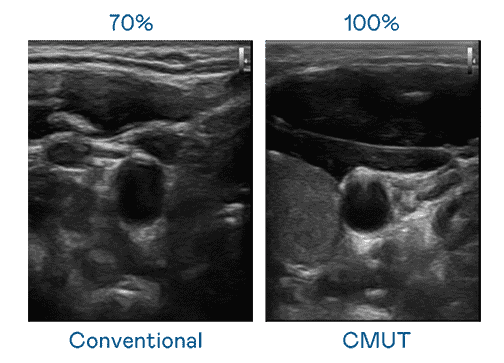

CMUT 技术是一种用电容式微机电元件来产生超音波讯号的技术。。。。与传统 PZT 压电式技术相比,,,,CMUT 频宽增加 30%,,,更宽频的超音波讯号让影像解析度大幅提升,,,,是实现高影像品质医疗超音波扫描、、、、促进精准医疗发展的关键技术。。

超音波影像的解析度高低,,,,首先取决于探头能发出的讯号频宽。。。传奇国际 CMUT 可提供高清晰的超音波讯号,,提供高频宽、、、高灵敏度、、、、影像纹理细节更高的超音波影像,,协助医护人员缩短影像判读时间及利用精准的医疗影像进行诊断。。